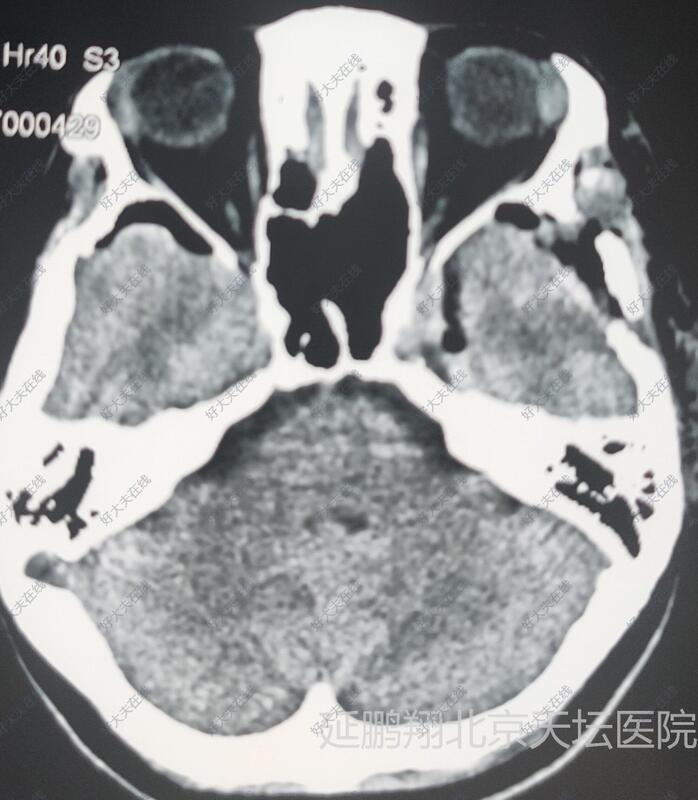

女性,48岁。发作性心悸,心烦,头晕11月。CT和MRI显示左侧鞍旁脑膜瘤,与海棉窦及颈内动脉及大脑中动脉关系密切。

术后病人全麻苏醒顺利,生命体征平稳,四肢活动好。常规术后六小时复查头颅CT显示肿瘤消失。